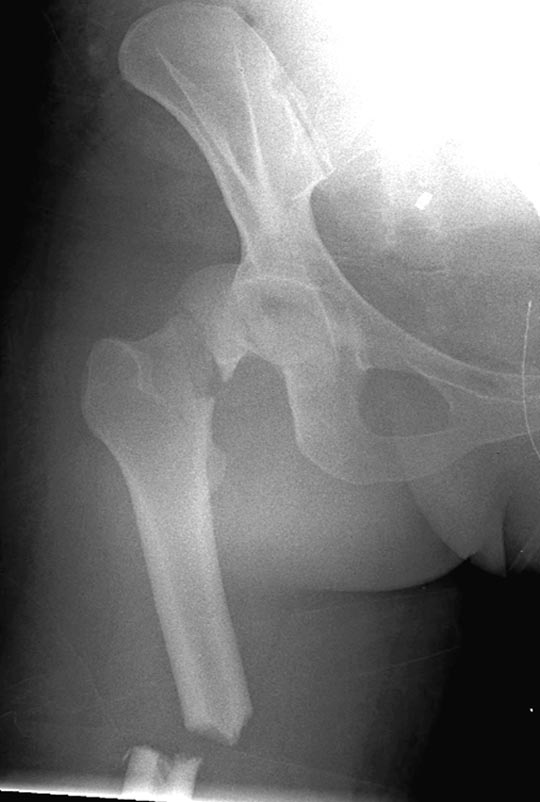

Здесь перечислены ортопедические повреждения: Rt. femoral shaft fracture, Rt femoral head fracture-dislocation, Rt distal femur fracture, Rt. open patella fracture, Rt. talus fracture dislocation, Rt. open humerus fracture, Left 5th metatarsal fracture, Left dislocation 1st TMT.

Во всех руководствах по политравмам рекомендуется подобный алгоритм, т.е. вправление вывиха и стабилизация длинных костей. В наших Травма центрах решение об ургентности операции принимает не Ортопед Травматолог, а ответственный Травма хирург!

В нашем случае с момента травмы прошло около 2 суток, и переломо-вывих бедра остается не вправленный. По нашим данным, риск осложнений при запоздалой репозиции остается высоким, и McKee 1998 также подтверждает, что репозиция вывиха бедра после 6 часов приводит к осложнению аваскулярным некрозом более чем 10%, а после 15.3 часов около 26%.

Фиксировать одним интрамедулярным гвоздем несколько переломов неплохая идея, но это не всегда удается. Для репозиции перелома шейки с вывихом головки (кстати, часть головки до сих пор остается внутри суставной впадины), потребуется много времени. Здесь каждый перелом требует особого подхода: например, для сохранения сферичности головки потребуется обширный доступ, а для остальных переломов различные трюки, что затрудняет фиксацию одним имплантатом!

На 25 день с момента травмы операция на Jackson table с боковым обширным доступом. Удаление стержней с местной обработкой. В тазобедренном суставе удаление головки, на дне вертлужной впадины полная отслойка хряща. Вертлужный компонент с одним винтом и короткая ножка - Fitmore press fit stem. На второй день однократно доза радиации для профилактики гетеретопической оссификации. Послеоперационный период без температуры. Выписана. Нагрузку разрешили на левой стороне, а полная в 3 мес. Здесь снимки при амбулаторном наблюдении: послеоперационно, 2 мес, 3 мес и 6 мес. Нагрузка полная, отсутствует хромота, и нет жалоб.